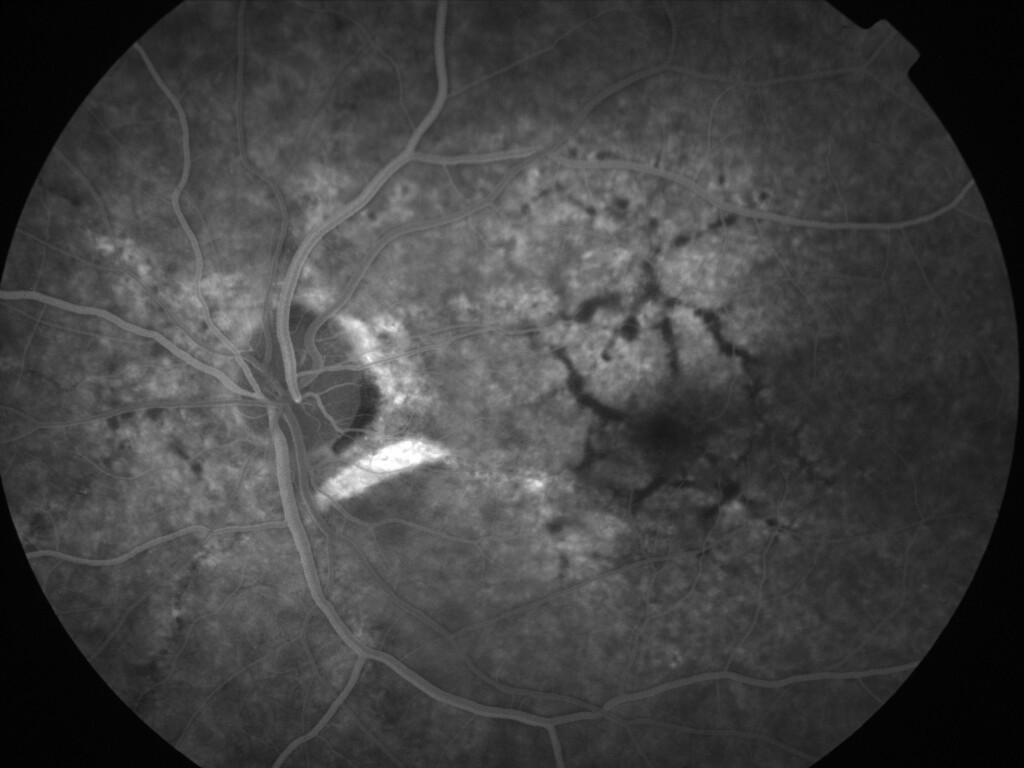

ASSOCIATION STRIES ANGIOIDES ET DYSROPHIE MACULAIRE RETICULEE

NEOVASCULARISATION